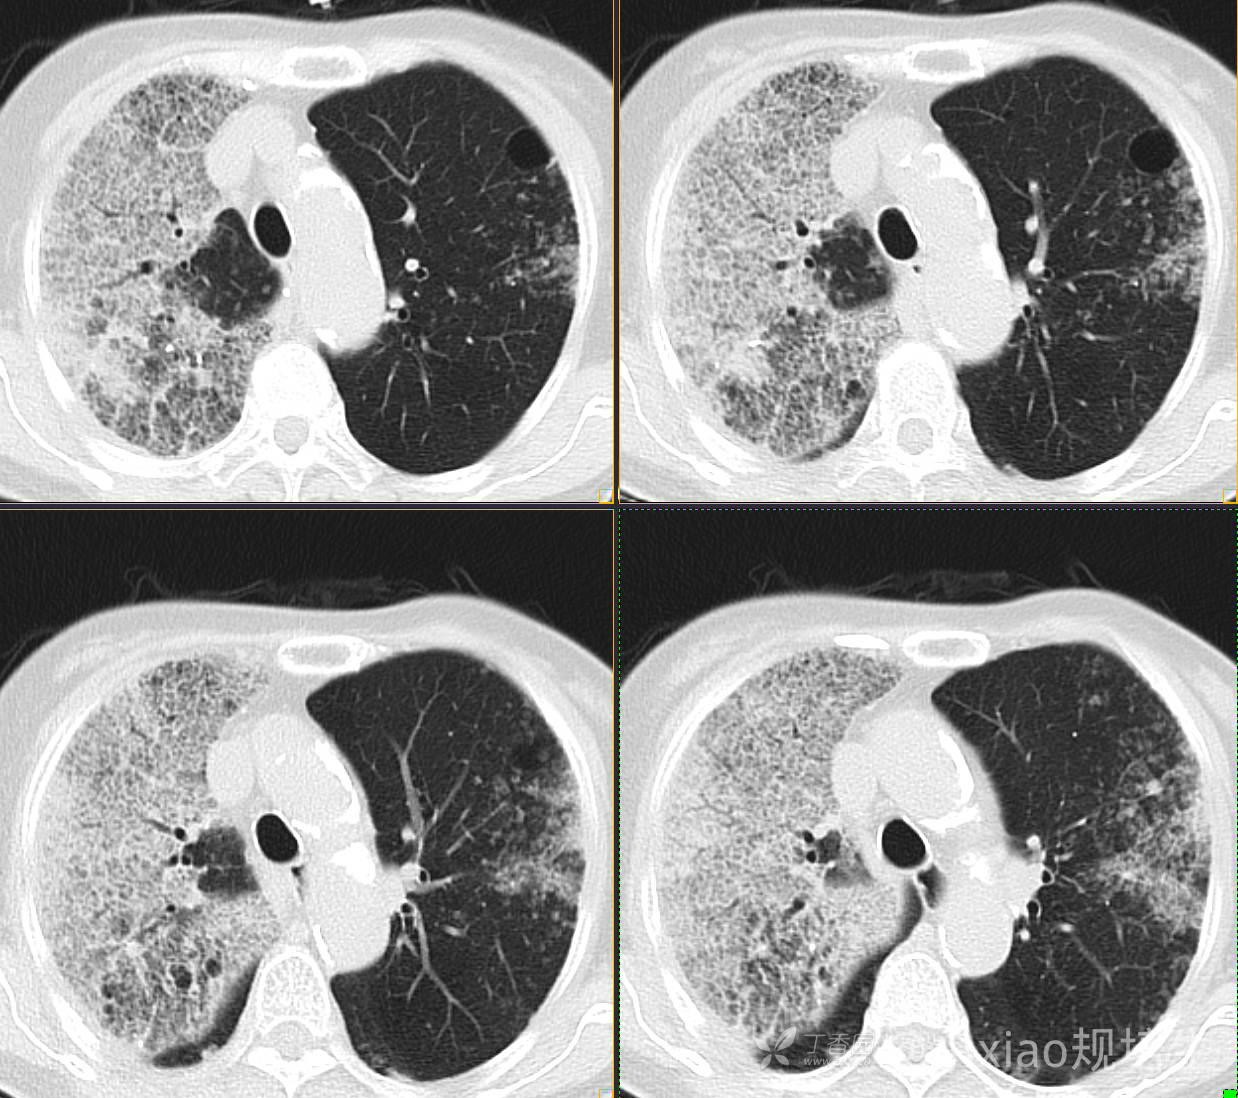

患者,女,89岁

咳嗽,咳痰一月余

肺泡蛋白沉着病 (19)